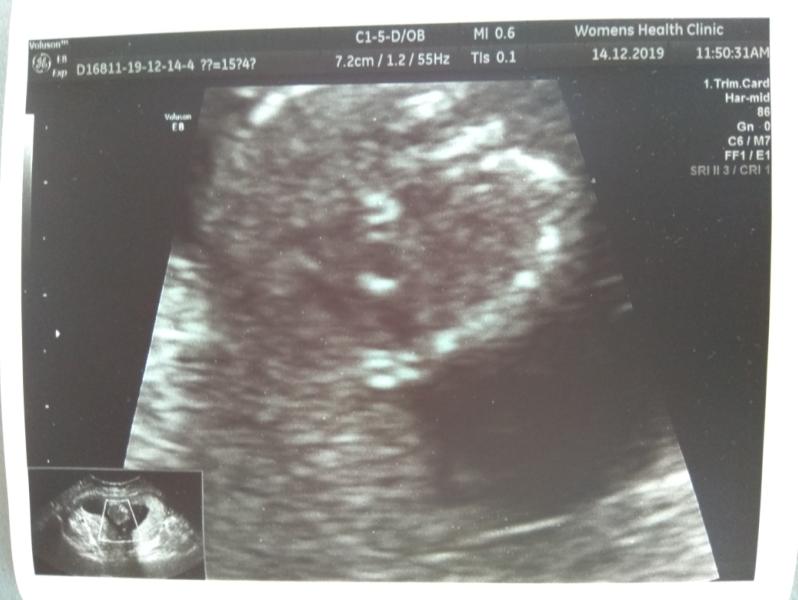

Девочки.. сегодня на УЗИ у малыша обнаружили ГЭФ левого желудочка сердца. Врач сказала, это может быть как от перенесенной инфекции, так и в худшем случае раковая опухоль. Контроль на 20й неделе. Места себе не нахожу(((

Спасибо за ответ! Была у Кусакиной в клинике женского здоровья. Отзывы вроде хорошие у нее..всё-таки схожу на УЗИ ещё раз, послушаю другого специалиста